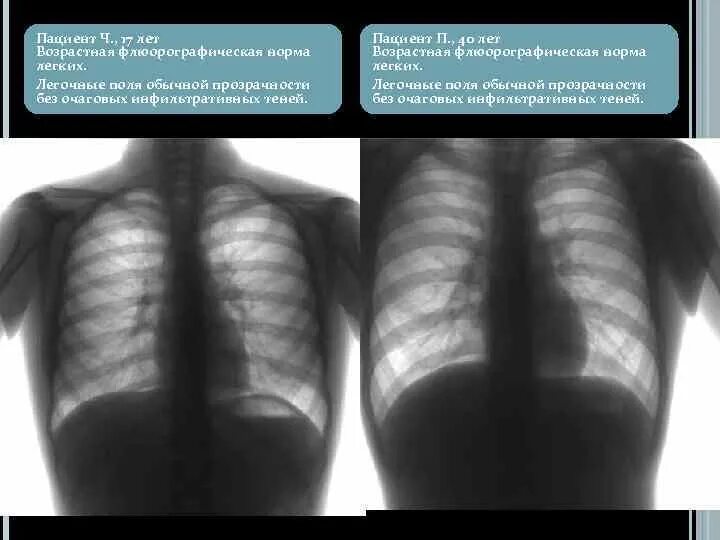

Легочные поля без очаговых и инфильтративных